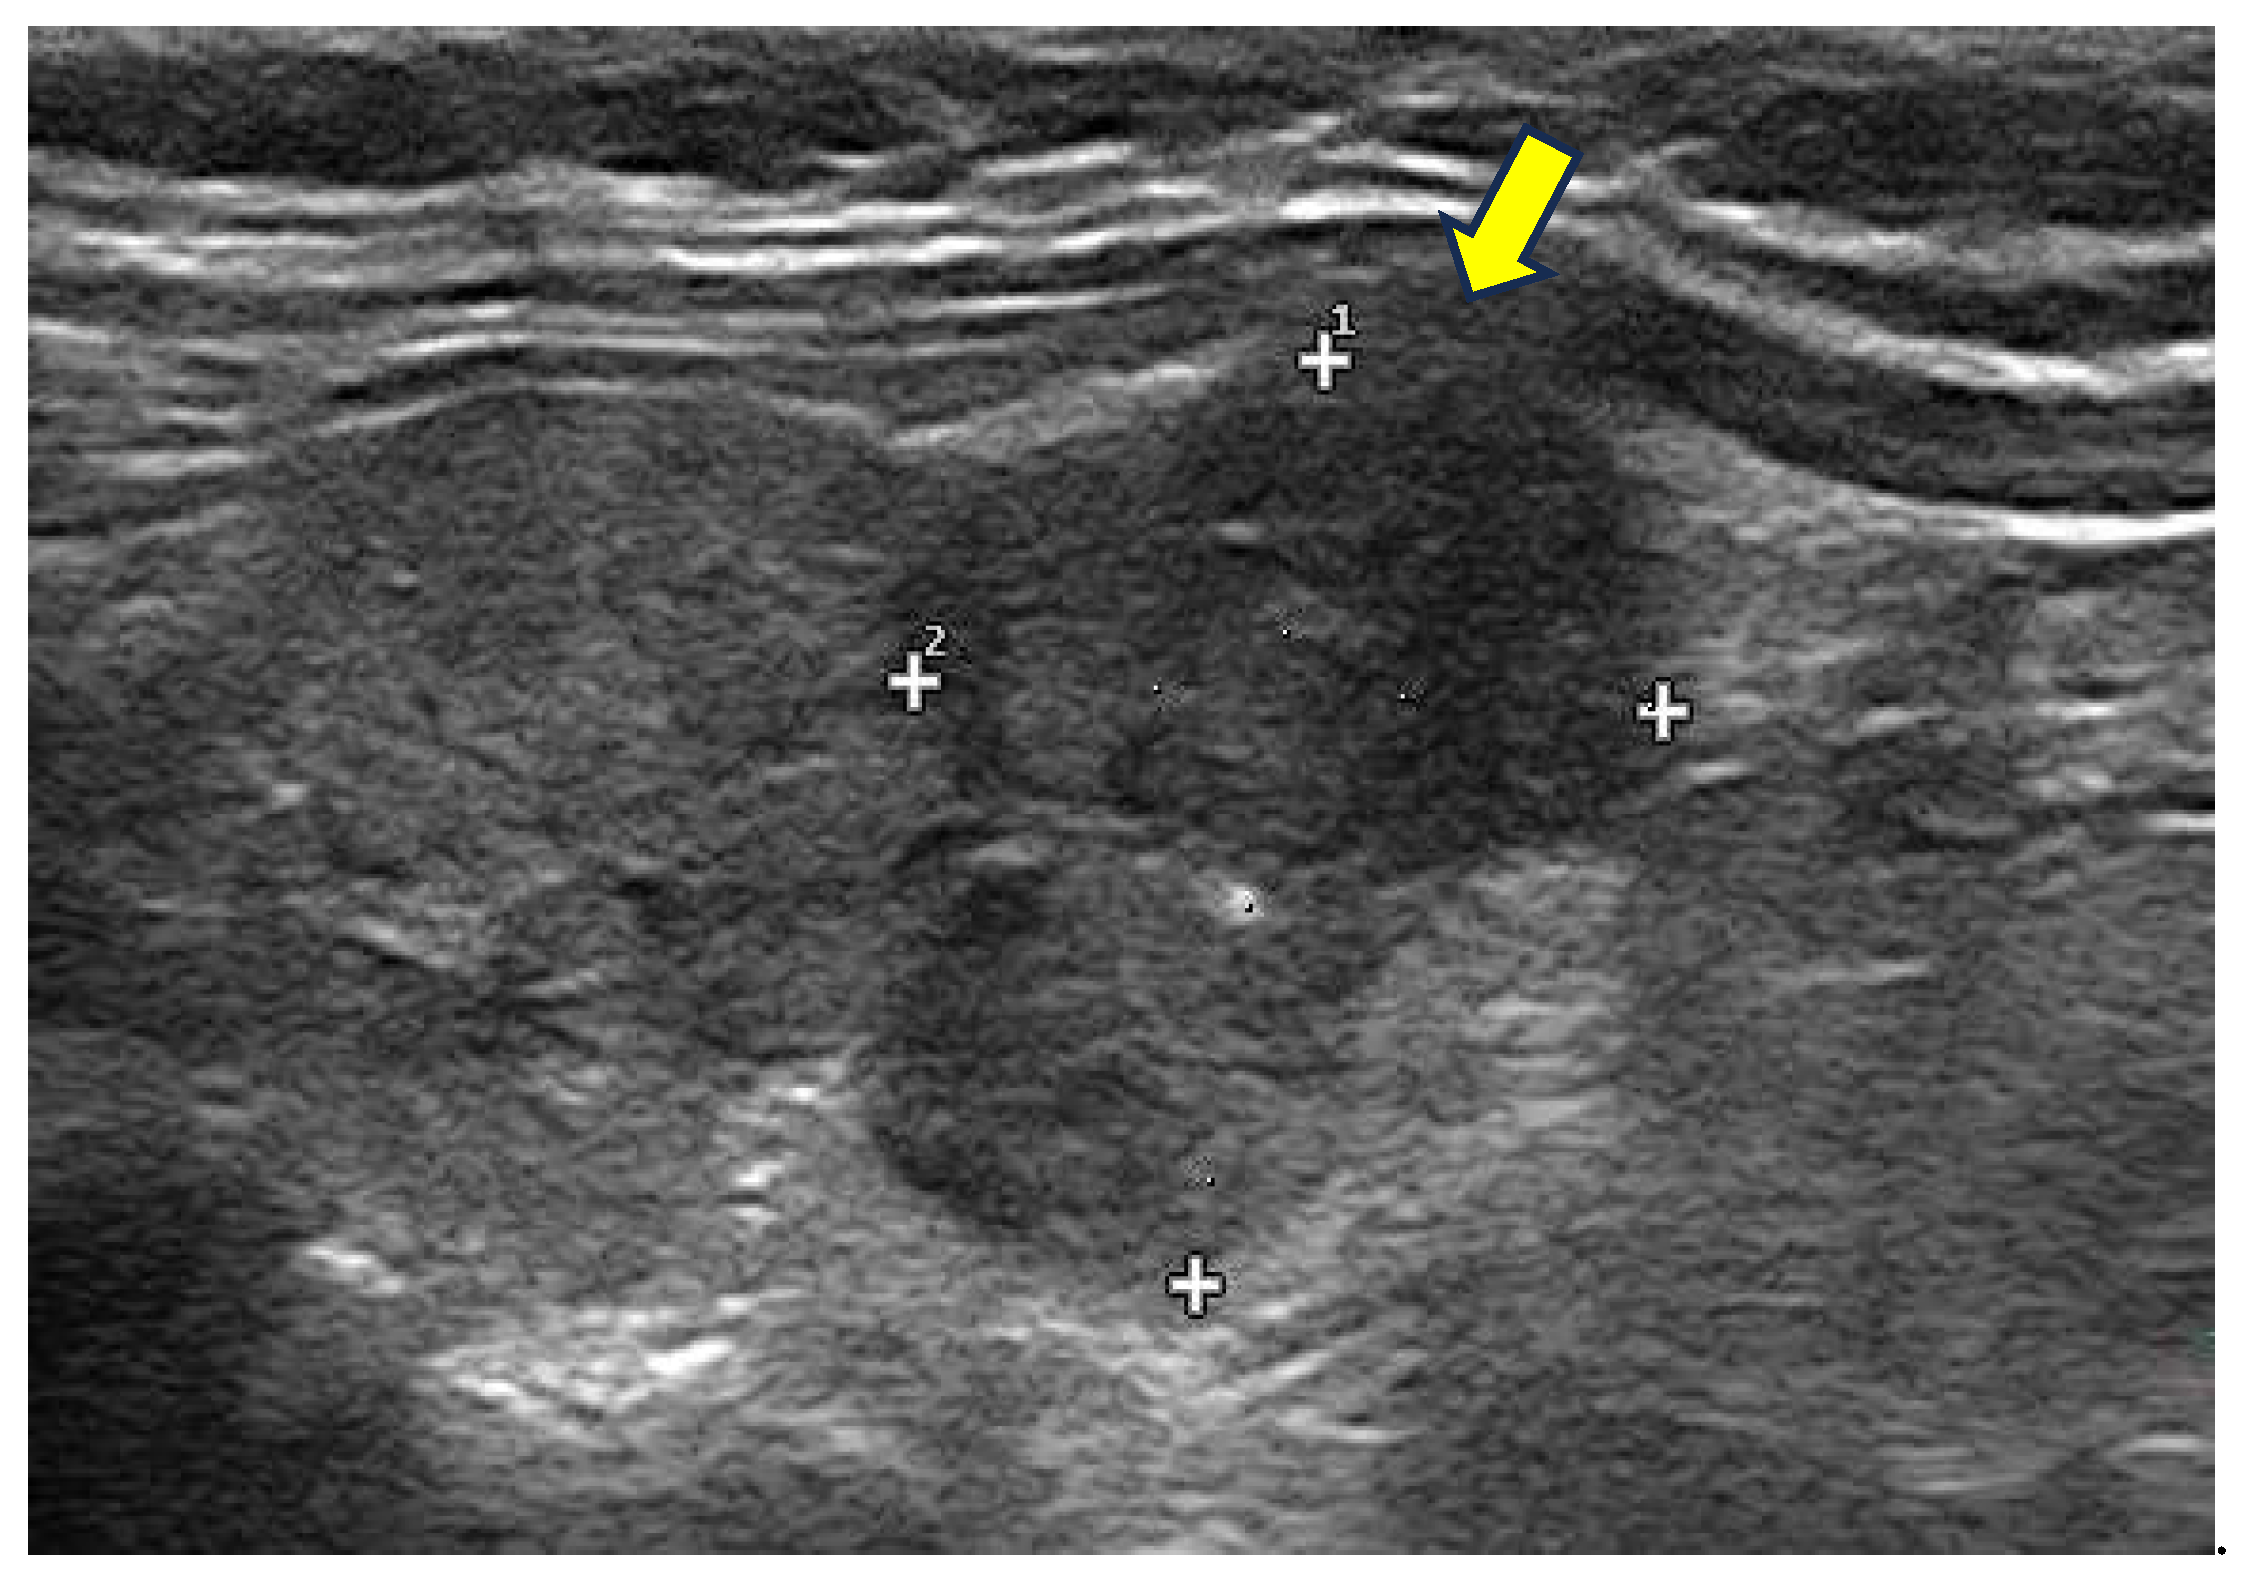

- Hypoechoic and heterogeneous texture: the thyroid tissue may display a hypoechoic and heterogeneous pattern due to inflammation and necrosis, particularly in subacute thyroiditis (Figure 2).